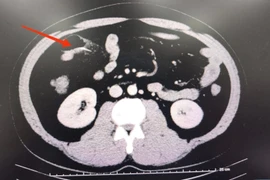

Mức độ bỏng: Bỏng điện độ III, IV, V tại vùng ngực, vai trái và đặc biệt là cẳng bàn tay phải.

Biến chứng: Chèn ép khoang cấp cẳng bàn tay phải. Do vết bỏng độ III, IV, V bao quanh cổ tay, bệnh nhân đang đứng trước nguy cơ cao phải cắt cụt cẳng tay phải.

Tình trạng hiện tại: Dù đã được phẫu thuật cấp cứu rạch mở khoang để giải áp, nhưng bàn tay phải vẫn tím tái, hồi lưu máu rất kém và thoát dịch nhiều.